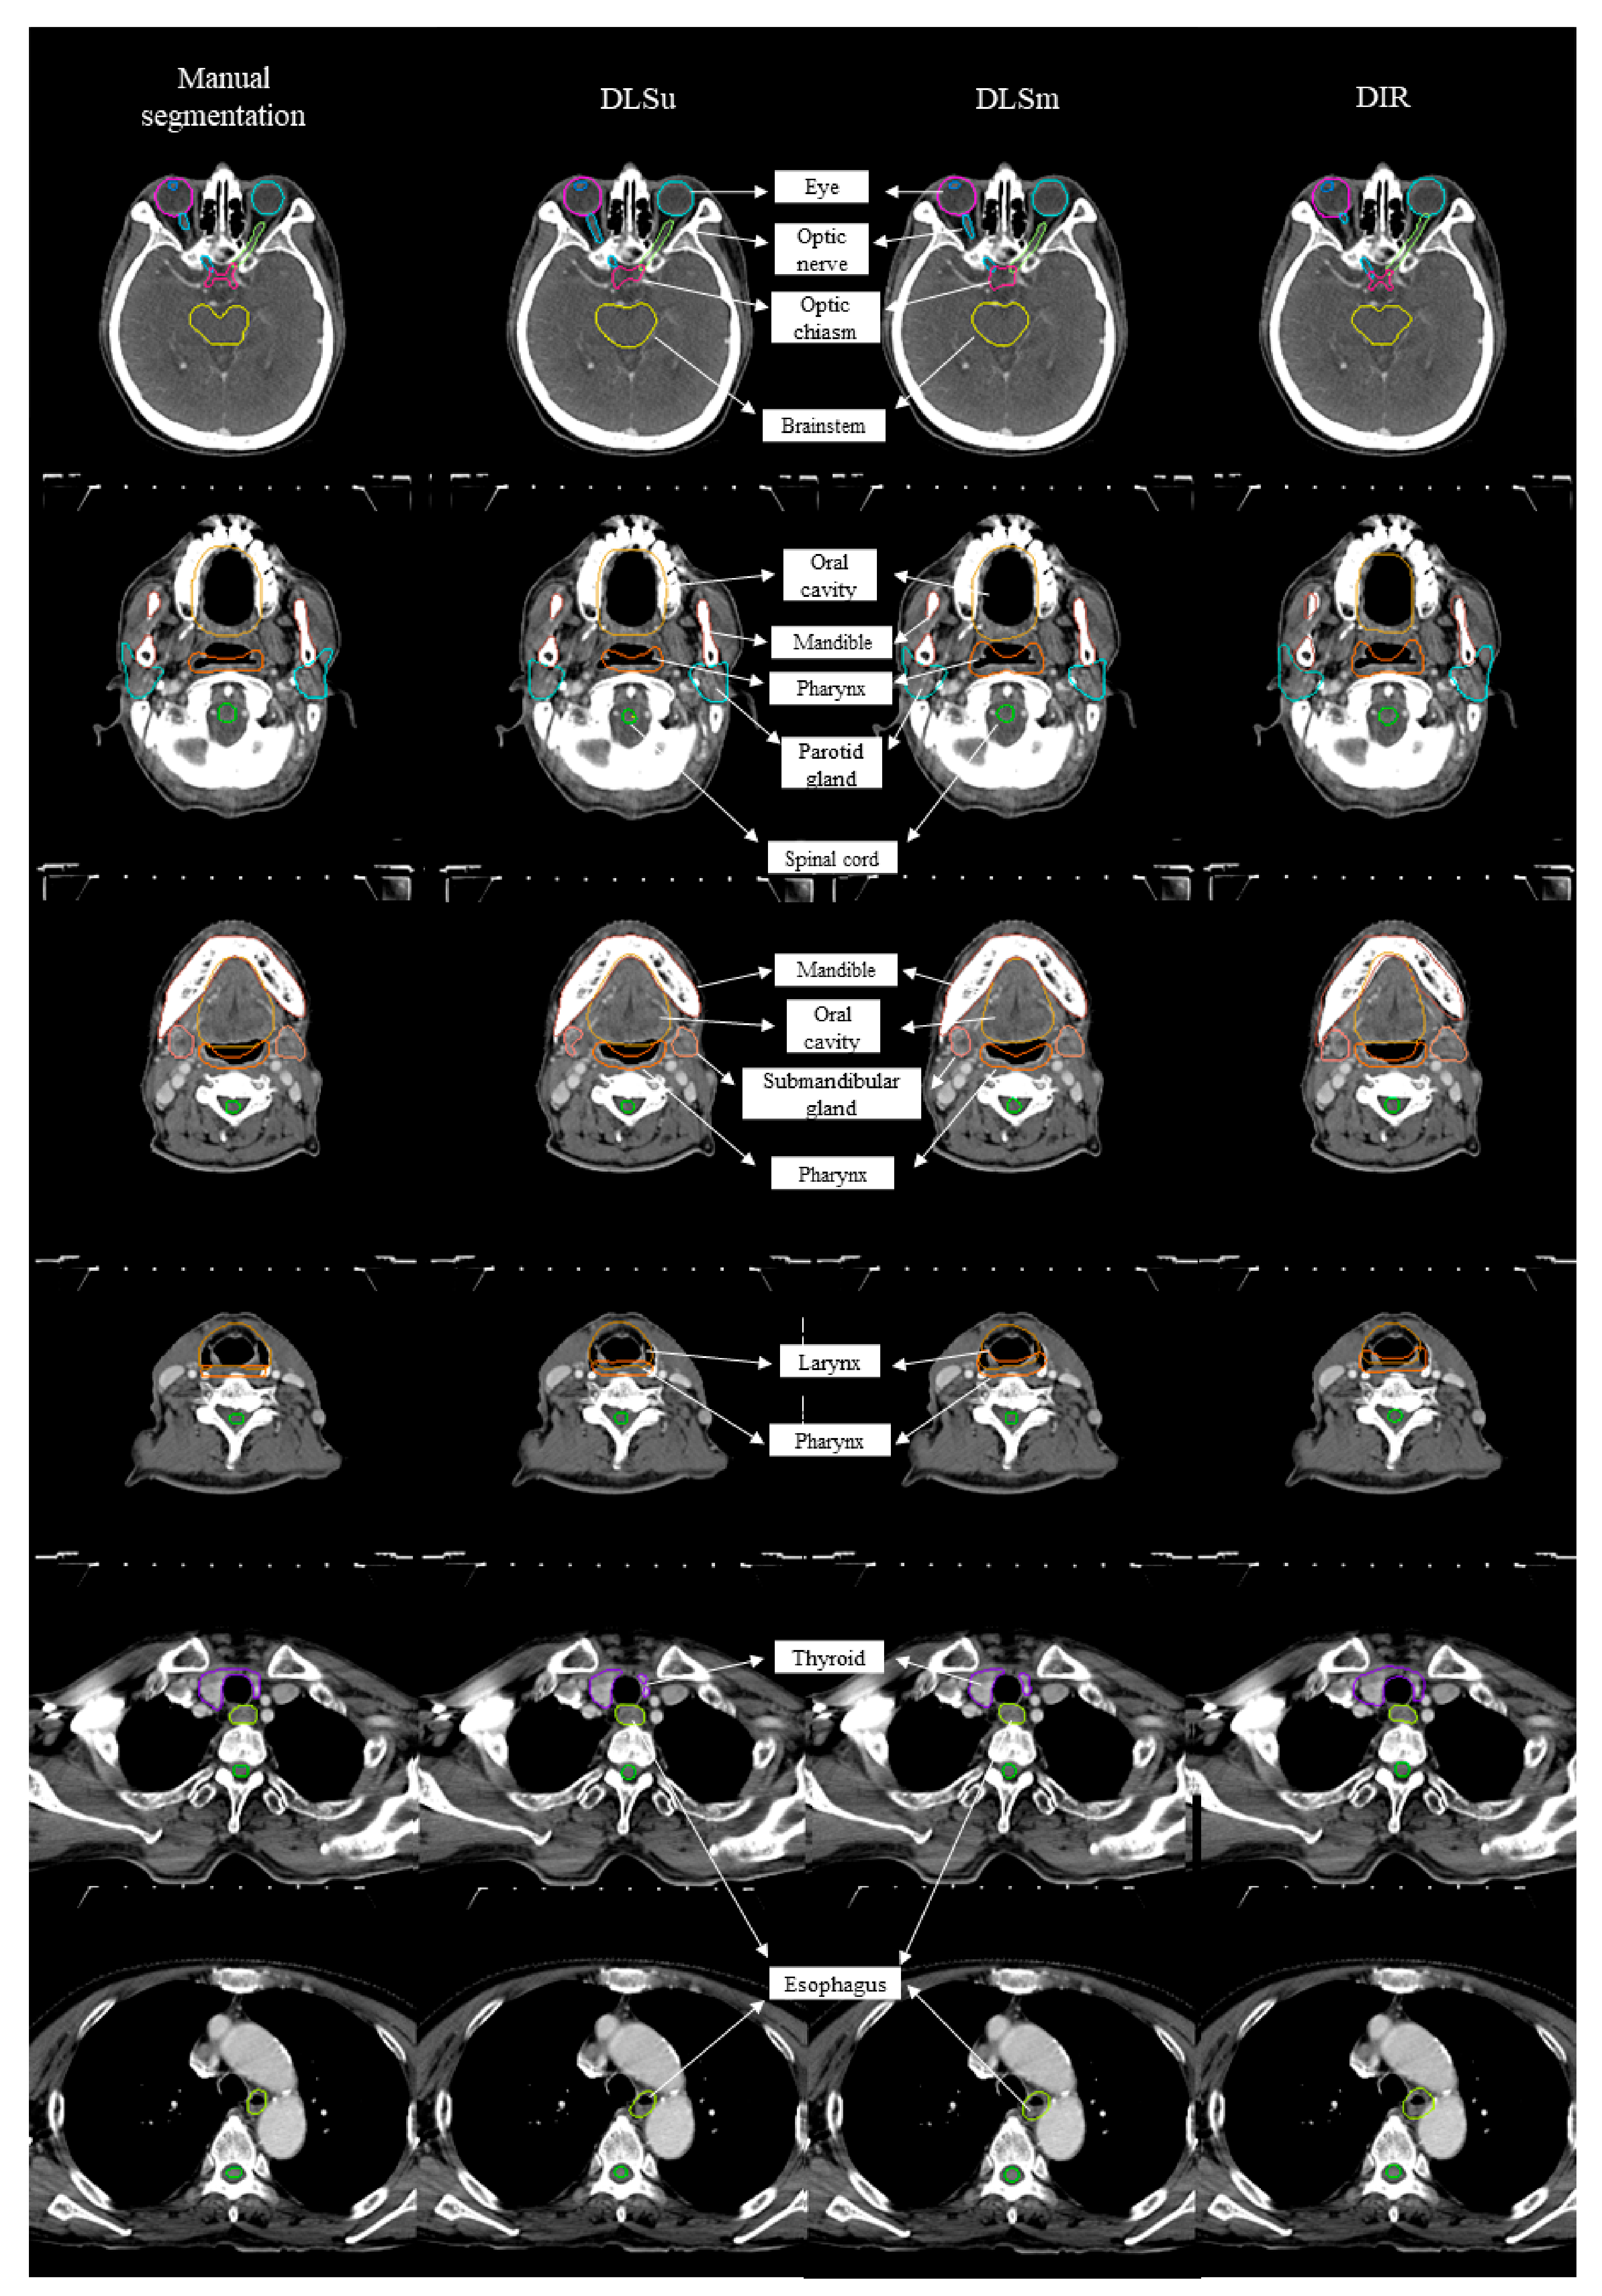

Figure 2 displays an example of DLSm, DLSu, and DIR. The averages for all tested values are summarized in Figure 3 and Table 1 and Table 2. The proposed DLS, irrespective of the training cohort, exhibited a better overall agreement with M than that shown by DIR, as evidenced by an increased mean DSC value (0.81 ± 0.02 vs. 0.70 ± 0.05, Figure 3A) with a reduced mean FPD (0.19 ± 0.03 vs. 0.33 ± 0.07, Figure 3B) and mean FND (0.19 ± 0.04 vs. 0.28 ± 0.05, Figure 3C). The HD and MSD values were also lower in the case of DLS compared with those exhibited by DIR (all p < 0.017, Figure 3D,E). Regarding the training set, DLSm exhibited minimally improved performance over that of DLSu, but the improvement was statistically significant (p < 0.017); here, the mean DSC increased from 0.80 ± 0.02 (DLSu) to 0.83 ± 0.02 (DLSm) with a significant reduction in FND (0.18 ± 0.03 vs. 0.20 ± 0.04, Figure 3C) rather than FPD (0.19 ± 0.03 vs. 0.19 ± 0.03, Figure 3B). In addition, DLSm minimally but statistically significantly reduced the distance between the automated and manual segmentation compared with that exhibited by DLSu (HD, 2.79 ± 0.22 vs. 3.04 ± 0.3; MSD, 0.98 ± 0.07 vs. 1.05 ± 0.10, Figure 3D,E).

Figure 2.

Examples of manual contour, deep learning-based segmentation based on the unmatched training set (DLSu) and matched training set (DLSm) and deformable image registration (DIR).